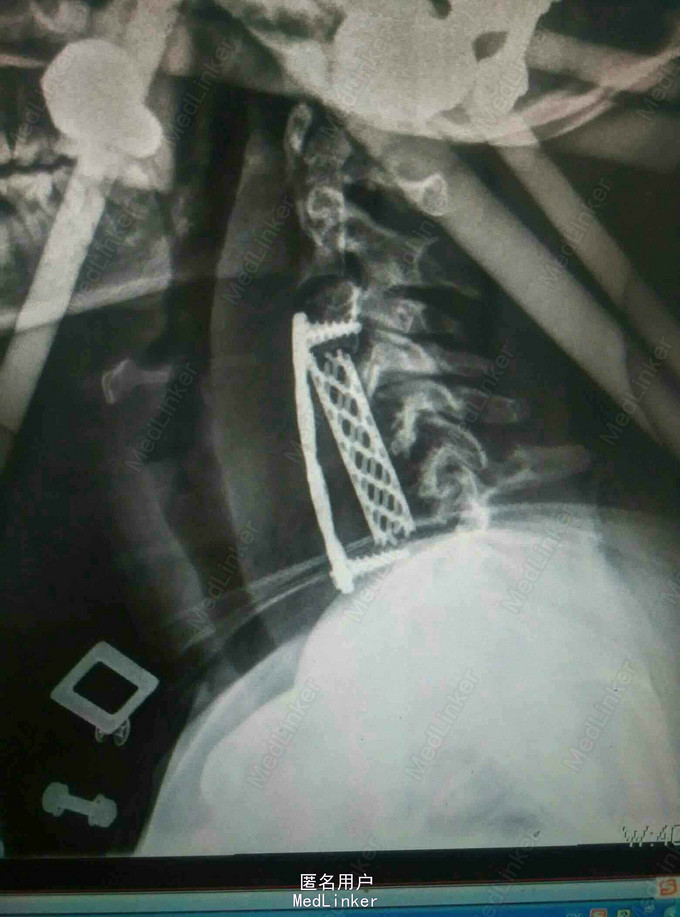

颈肩痛伴左侧肢体无力5月 患者青年男性,无明显诱因出现颈肩痛,性质钝痛,伴有左侧肢体无力,症状反复发作五月。于当地医院就诊查核磁提示颈椎结核,椎旁脓肿。患者二便正常,既往结核病史。

查体:颈椎生理弯曲消失,各棘突及椎旁压痛,胸腰椎生理弯曲不在,各棘突无压痛,椎旁无叩击痛。左侧肢体肌力降低,双侧Hoffoman征阳性,Babinski征阳性。 辅查:我院磁共振提示颈椎结核并椎旁脓肿,颈椎失稳。

诊断:颈椎结核伴椎旁脓肿 颈椎不稳 四肢不全瘫。 治疗:颈前路病灶清除植骨融合内固定术+Halos架固定,术后护肝抗结核治疗